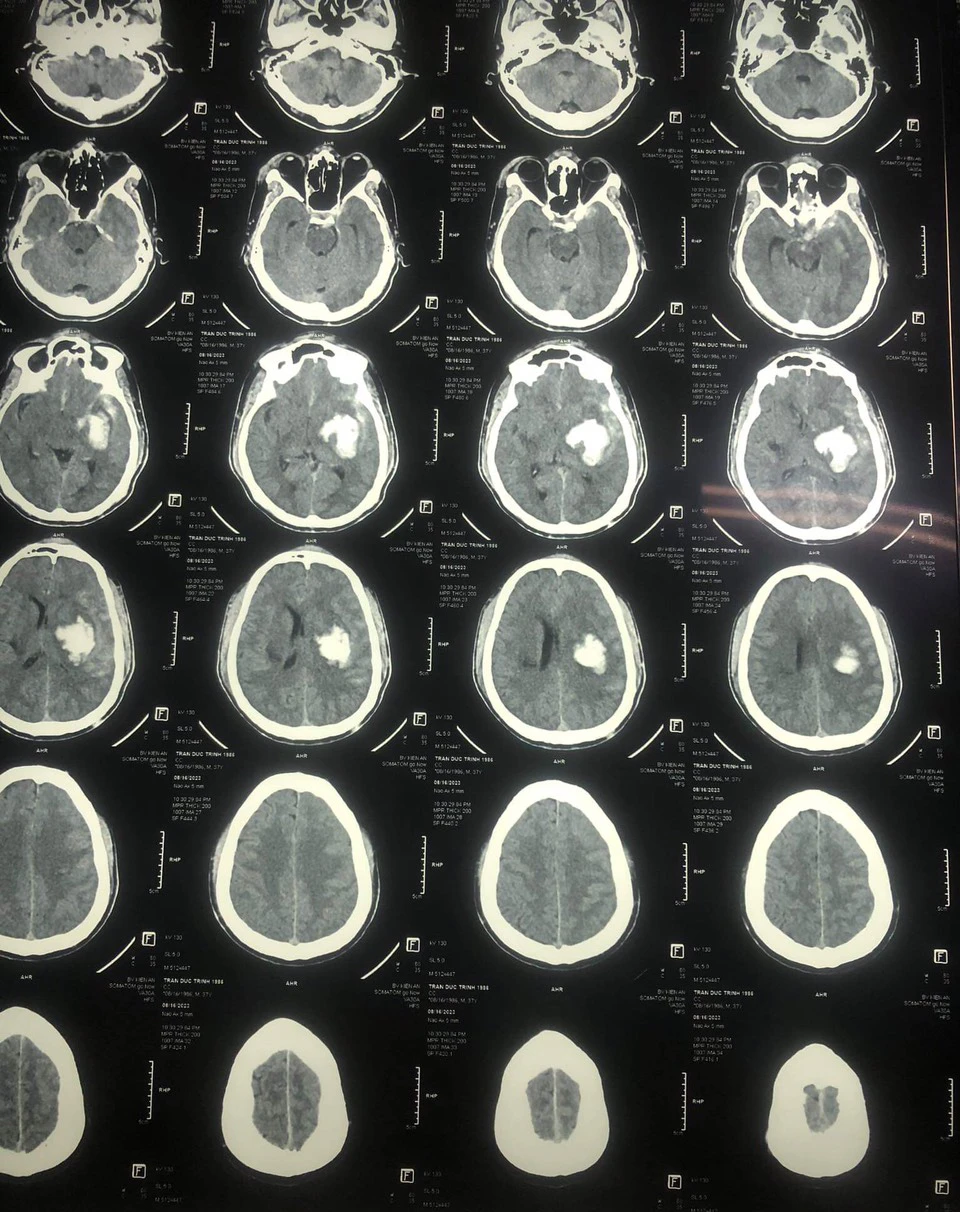

"Lúc đấy anh tôi trong tình trạng hôn mê, mặt mũi bầm dập, tím tái. Bác sĩ chẩn đoán anh Trình bị tụ máu não, chấn thương vùng mặt, gãy 3 xương sườn bên trái" - anh Sang kể

Sau đó, anh Trình được chuyển đến Khoa Phẫu thuật Thần kinh và Sọ não, rồi trưa 18-8 được phẫu thuật. “Đến giờ là hơn 3 ngày sau đại phẫu, anh tôi vẫn đang hôn mê. Các bác sĩ nói rằng anh tôi bị tụ máu não, tiên lượng xấu, dù phẫu thuật thành công thì sau này cũng không thể tỉnh táo được như bình thường, thậm chí có khả năng bị liệt nửa người”.

| Hình ảnh chụp thương tích xuất huyết bán cầu trái của bệnh nhân Trần Đức Trình |

Cùng với đó, kết quả chụp cắt lớp sọ não của Trình ghi nhận có chảy máu bán cầu trái, tổn thương cũ nhu mô bán cầu phải và một số vết bầm nhỏ trên mặt. Cung trước các xương sườn trái số 7, 8, 9 có vết gãy cũ, đang trong giai đoạn liền xương.

Kết quả thăm khám của cơ quan y tế cũng cho thấy bệnh nhân Trình không có dấu hiệu tổn thương xương hộp sọ cũng như các tổn thương khác do tác động ngoại lực.